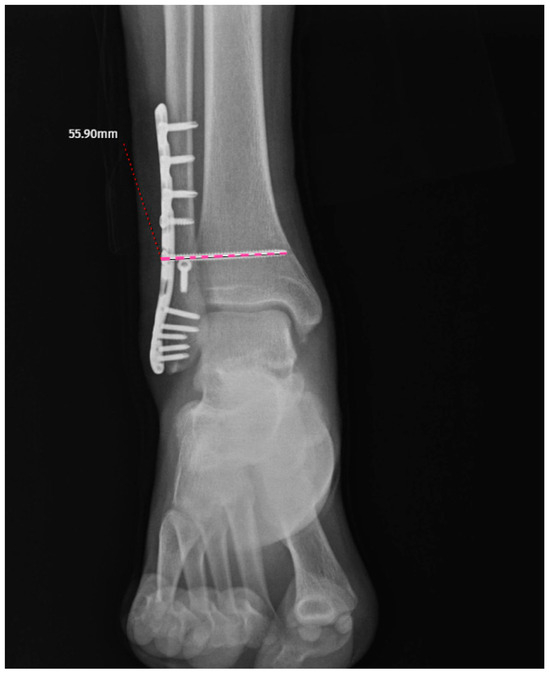

Radiographic and Demographic Factors Associated with Syndesmotic Screw Breakage in Ankle Fractures

by Emre Kocazeybek, Mehmet Ekinci, Salih Magi, Murat Altunsoy, Kubilay Yolaçan, Murat Yılmaz and Mehmet Ersin

J. Clin. Med. 2026, 15(7), 2647; https://doi.org/10.3390/jcm15072647 - 31 Mar 2026

Background: Syndesmotic screw breakage is a well-recognized mechanical complication following ankle fracture fixation. Although several studies have investigated patient-related and technical factors associated with screw breakage, the temporal pattern of screw failure and implant survival remains less clearly defined. Therefore, this study aimed [...] Read more.

Background: Syndesmotic screw breakage is a well-recognized mechanical complication following ankle fracture fixation. Although several studies have investigated patient-related and technical factors associated with screw breakage, the temporal pattern of screw failure and implant survival remains less clearly defined. Therefore, this study aimed to evaluate one-year syndesmotic screw survival using time-to-event analysis and to identify factors associated with screw breakage. Materials and Methods: A total of 132 patients with unstable AO-Weber 44-B/C ankle fractures treated with syndesmotic screw fixation were retrospectively analyzed. Patients were followed for a minimum of 12 months or until screw breakage occurred. Screw survival was evaluated using Kaplan–Meier analysis and Cox proportional hazards regression was performed to identify factors associated with screw breakage. Demographic variables, fracture type, and screw-related parameters were analyzed. Receiver operating characteristic (ROC) analysis was used to assess the discriminative ability of age. Results: Screw breakage occurred in 31 patients (23.5%) during follow-up. Kaplan–Meier analysis demonstrated significantly lower screw survival in Weber C fractures compared with Weber B fractures (log-rank p < 0.001). Cox regression analysis identified younger age (HR: 0.965, 95% CI: 0.937–0.993, p = 0.016) and Weber C fracture type (HR: 1.811, 95% CI: 1.260–2.602, p = 0.001) as independent predictors of screw breakage. ROC analysis showed that age had moderate discriminative ability (AUC: 0.719, 95% CI: 0.612–0.816), with a cut-off value of 35.5 years. Conclusions: Younger age and Weber C fracture type are associated with an increased risk of syndesmotic screw breakage and Weber C fractures also demonstrating reduced screw survival. These findings may assist in patient counseling; however, the clinical implications of screw breakage remain uncertain. Full article